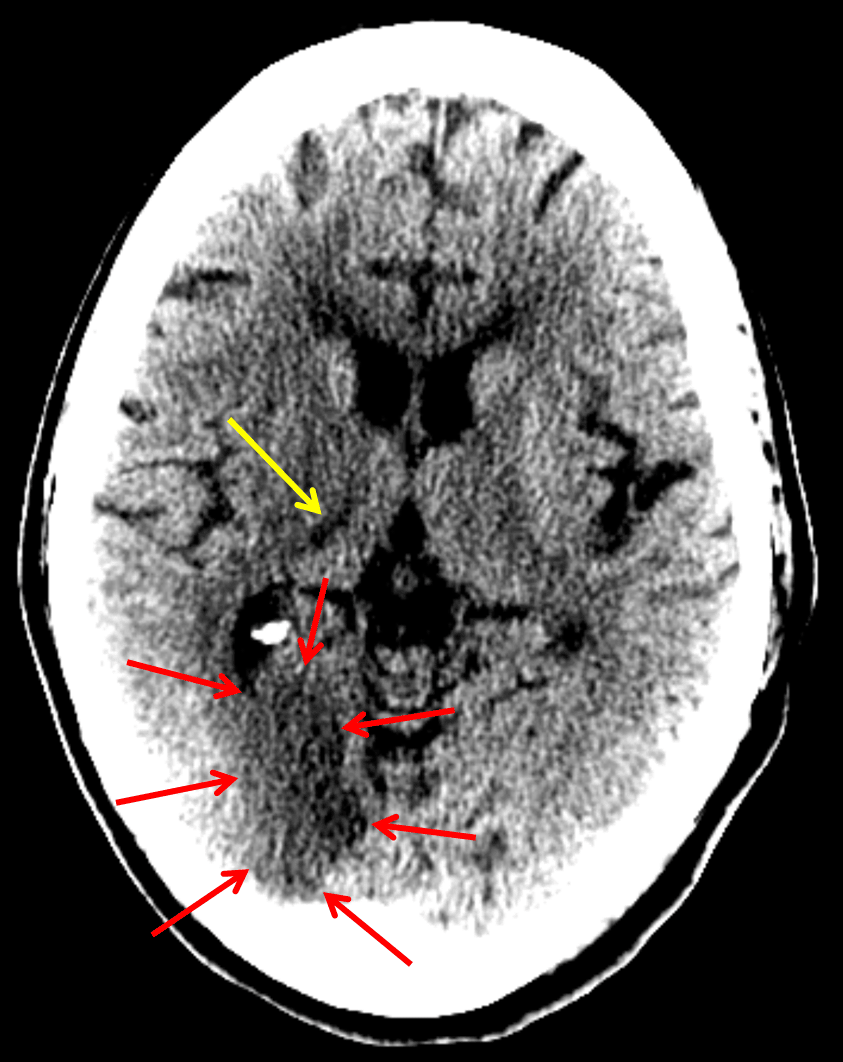

Findings

- Hypoattenuation with loss of gray-white differentiation in the right PCA territory, including the right occipital lobe and ventrolateral right thalamus

Right PCA territory infarct

Sample Report

Hypoattenuation and loss of gray-white differentiation in the right occipital lobe concerning for acute/early subacute ischemia. Hypoattenuation in the ventrolateral right thalamus represents an age-indeterminate infarct. Both of these areas are in the right PCA territory. MRI could further assess the extent of infarct.

No mass effect or evidence of hemorrhagic transformation.

Annotated Images & Illustrations

Red arrows: acute/early subacute infarct in the right occipital lobe. Yellow arrow: age-indeterminate right thalamic infarct (looked acute on the subsequent MRI)